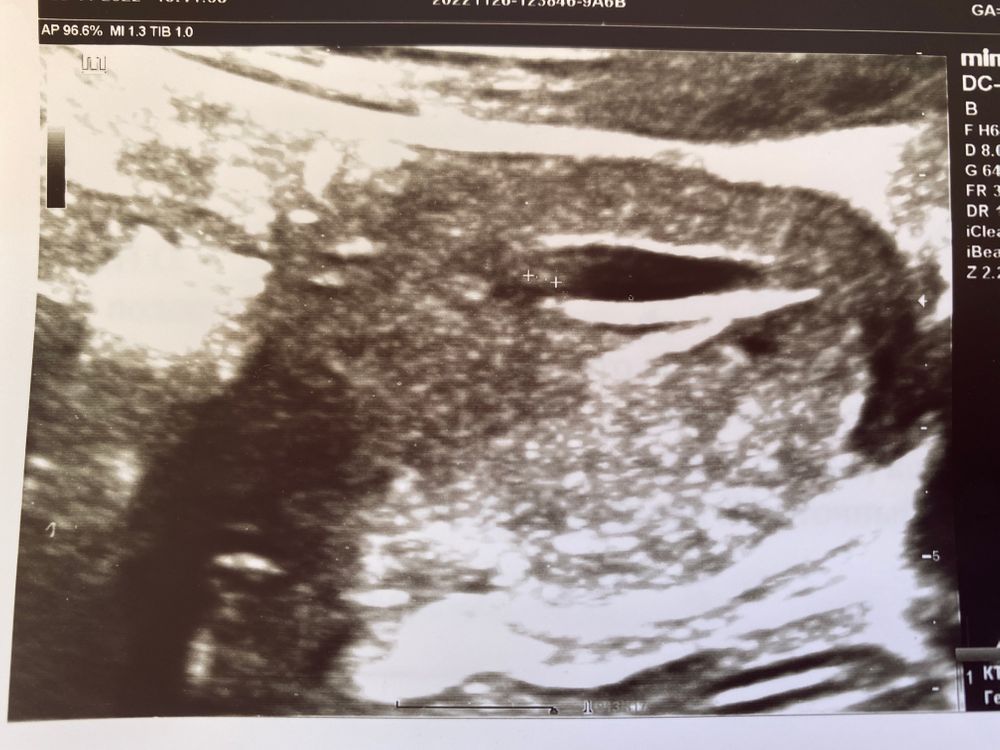

Здравствуйте! По УЗИ поставили 5 недель 5 дней. Врач сказал, что все в порядке - беременность маточная, лишней жидкости нет, прослушивается сердцебиение, КТР плода 2,2 мм, СВД плодного яйца 12 мм, хорион по передней стенке, тонус нормальный, желточный мешок 2,0 мм. Я прочитала, что плодное яйцо в норме имеет овальную или округлую форму, а у меня как будто вытянутое, а это считают тонусом, что плохо. Чувствую я себя хорошо, только редко бывает небольшое напряжение в области живота, иногда как будто немного тянет внизу. Есть ли какие-то отклонения по УЗИ или все показатели в норме? Считается ли такая форма плодного яйца, как у меня, деформированной?

Это результат повышенного тонуса матки. Сравните на снимках толщину передней и задней стенок матки. И Вы убедитесь, что я, к сожалению, права. Вам надо в течение 2-х недель соблюдать постельный режим и пока воздержаться от близости. Принимайте таблетки Но-шпа, или Дротаверин, по 2 таблетки на прием, при тянущих болях в низу живота, если боли не беспокоят, не надо принимать ни Но-шпа, ни Дротаверин. Вместо таблеток, расслабляющих мышцу матки, можно вводить в задний проход свечи с папаверином (родственник Дротаверина). Но свечей можно ввести не более 2-х в день, а если возникнет необходимость, можно принять до 10 таблеток . Дополнительно подключите гормональную поддержку беременности - драже Утрожестан, вводите вагиинально по 200 мг на ночь до 8 недель, когда надо будет его постепенно начать снижать, чтобы не угнетать развитие плаценты. И начните прием поливитаминов дл беременных Элевит 1 триместр или Фемибион-1.